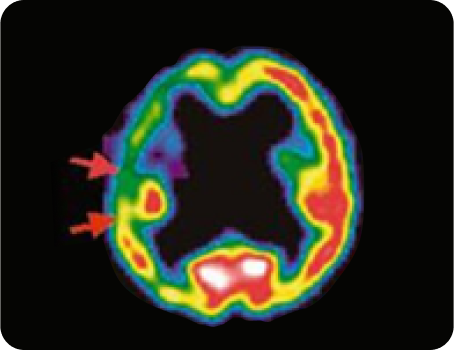

우측 중대뇌동맥 폐색 환자의 3주 후

SPECT(뇌 혈류 역학 검사) 사진

침 치료 8일 후 증가된 혈류

침 치료 후 증가된 뇌경색 주변부 혈류량